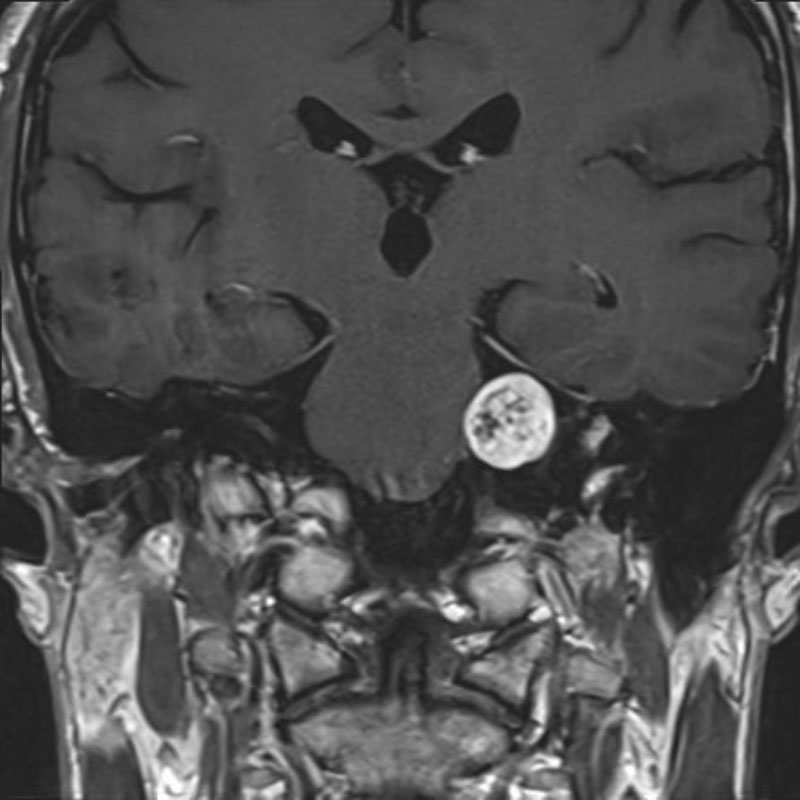

頭蓋咽頭腫

頭蓋内腫瘍摘出術

No.’25_96 手術前1

No.’25_96 手術前2

No.’25_96 摘出 前

No.’25_96  摘出 中

No.’25_96 摘出 後